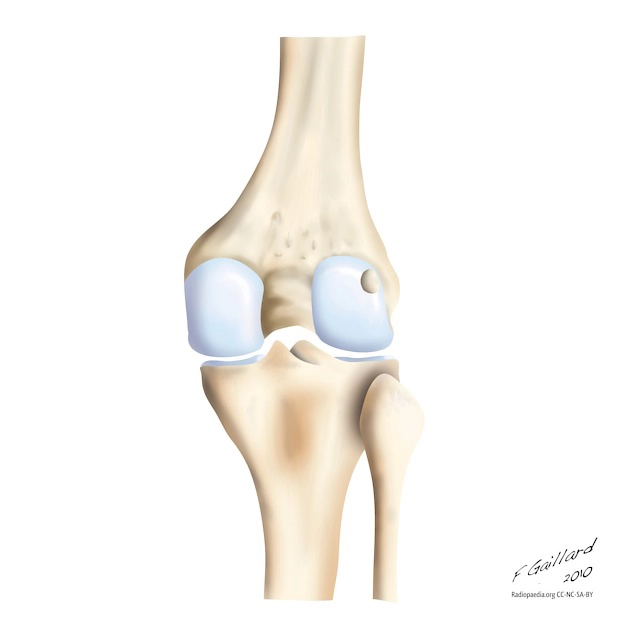

• Cơ xương khớp

• Khớp gối

• Gãy bong khớp gối